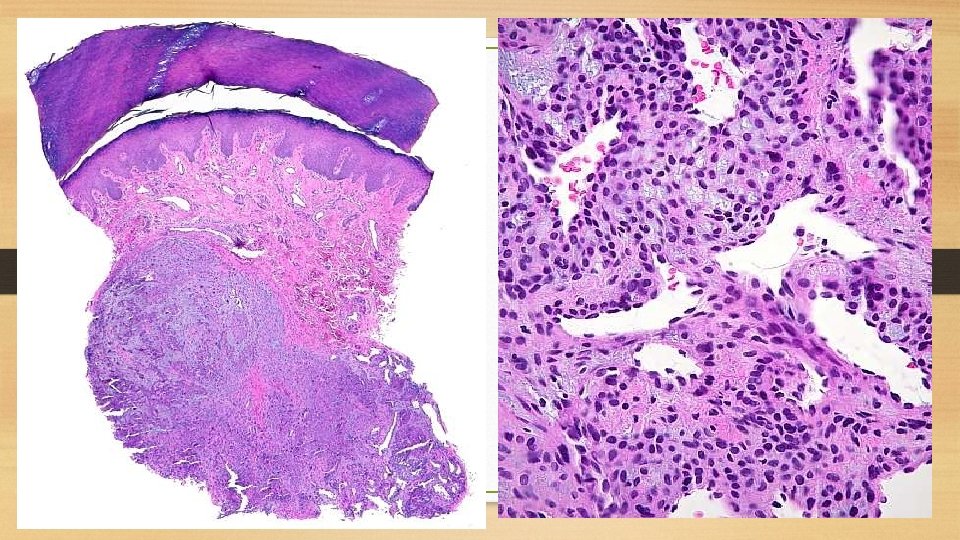

Haemangioendothelioma It is found most often in the skin and subcutaneous tissue in relation to medium-sized and large veins but can be found in internal organs as liver and lung. Gross picture: The tumor is usually well-defined, greyish red, polypoid mass. Microscopic picture: There are proliferated endothelial cells forming several layers around the blood vessels so that vascular lumina are difficult to identify.